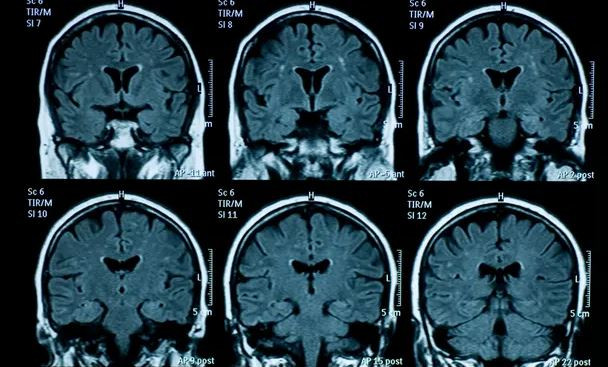

Dấu hiệu lão hóa sớm ở não bộ thanh thiếu niên sau đại dịch COVID-19 ảnh 1Sức khỏe tâm thần giảm sút đi đôi với những thay đổi về cấu tạo vật lý của não bộ ở thiếu niên. (Nguồn: Getty Images)

Các nhà nghiên cứu đã so sánh hình ảnh chụp cộng hưởng từ (MRI) của 81 thanh thiếu niên sống tại Mỹ được chụp trước thời kỳ đại dịch bùng phát (từ tháng 11/2016-11//2019) với kết quả MRI của 82 thanh thiếu niên chụp trong giai đoạn từ tháng 10/2020-3/2022, khi đại dịch vẫn hoành hành nhưng sau khi các biện pháp phong tỏa đã được dỡ bỏ.

Sự thay đổi về cấu trúc vật lý của não bộ trong quá trình dậy thì - như vỏ não mỏng đi, sự phát triển của đồi hải mã và chất xám - xảy ra ở nhóm được chụp MRI sau phong tỏa nhiều hơn so với nhóm được chụp MRI trước đại dịch.

Giáo sư chuyên ngành tâm lý học của đại học Standford, Ian Gotlib, tác giả chính của nghiên cứu, cho biết chênh lệch về mức độ lão hóa não bộ giữa 2 nhóm là khoảng 3 năm.